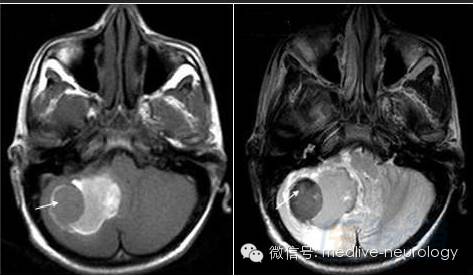

然后解决第三个问题,轻松一下,图来啦,让我们巩固一下今天学习的成果,均为先T1,后T2。

慢性期(>14d):箭头